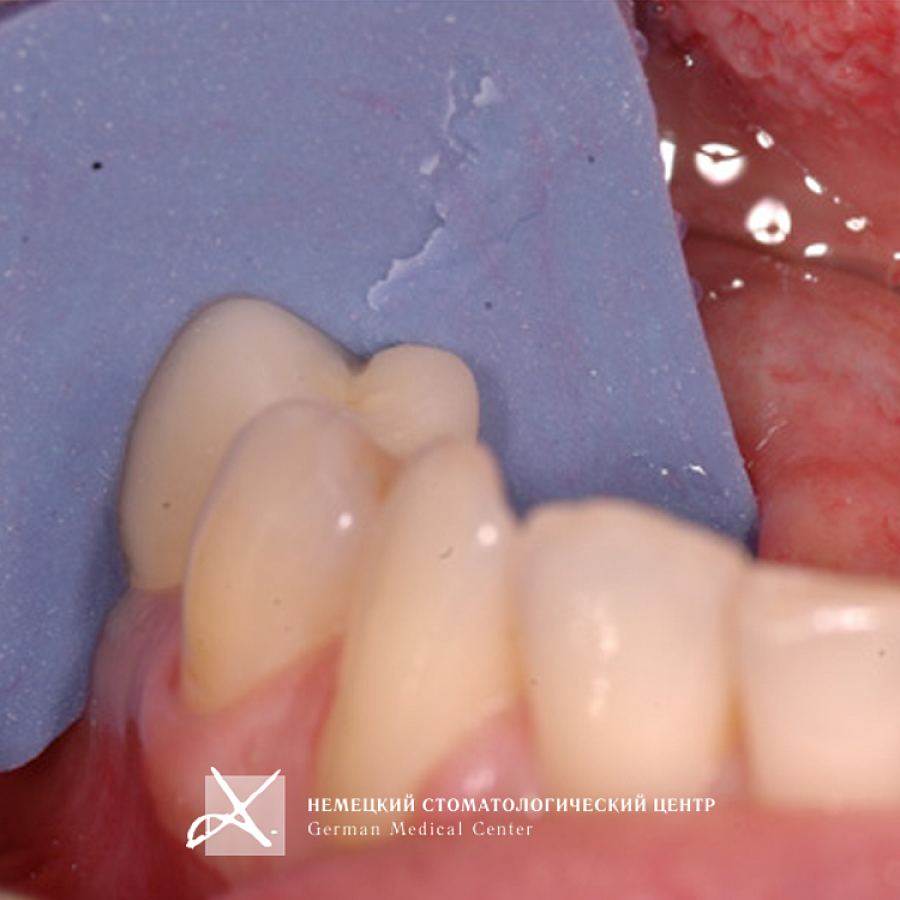

Учитывая тот факт, что диаметр имплантата практически всегда вынужденно меньше диаметра восстанавливаемого зуба в данной анатомической области, чтобы получить максимально эстетический и функциональный результат, было сделано:

- Поэтапное "выстраивание" десневого контура ("кратера прорезывания") с помощью индивидуально моделируемой диагностической промежуточной коронки и индивидуально построенной супраструктуры (абатмента), выполненной из золотосодержащего сплава.

- На индивидуальный абатмент зацементирована эстетическая керамическая коронка.